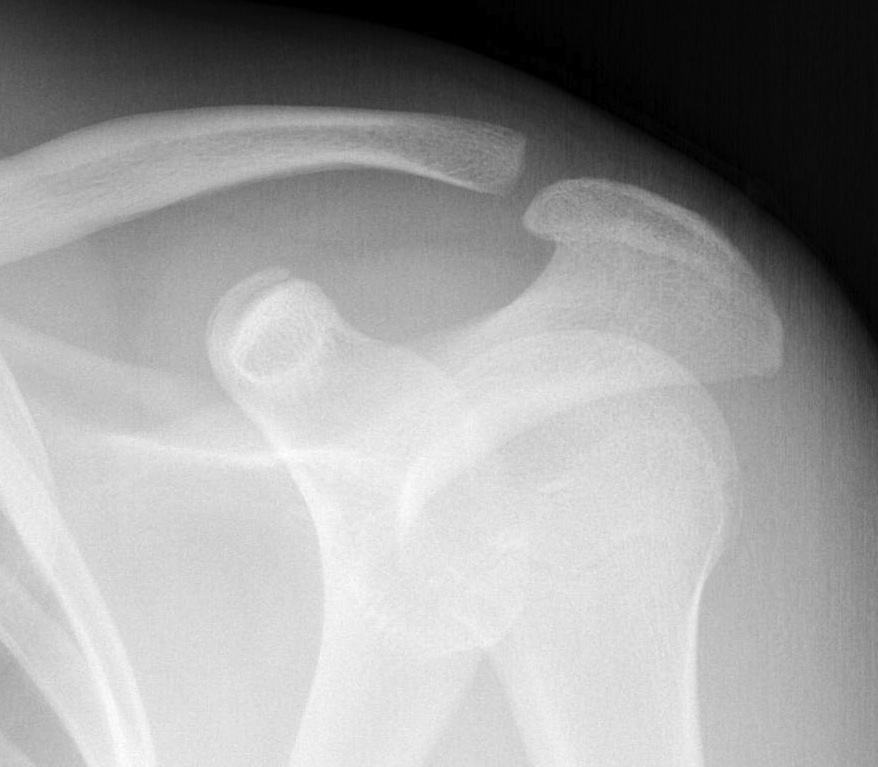

V High dislocation (100 - 300% CC distance) - disrupted trapezius & deltoid and end of clavicle subcutaneous

VI Subcoracoid dislocation

Type VI / Subcoracoid dislocation

Rare / can be missed

Risk of neurovascular injury / high velocity injury / associated with multi-traumas

Requires open reduction and fixation

- will have to release soft tissue off coracoid if not already avulsed

- i.e. pectoralis minor / coracoacromial ligament

- attempt to reduce with lateral traction of arm

- may need to release conjoint / perform coracoid osteotomy

- stabilize as needed

Subcoracoid dislocation case report